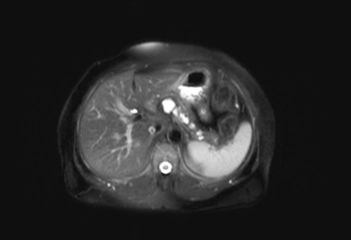

Bu belirtiler, lezyonun yerleşim yeri ve büyüklüğüne göre değişiklik gösterebilir. 4. Tanı YöntemleriYoğun içerikli kistik lezyonların tanısı, çeşitli görüntüleme yöntemleri ve biyopsi ile yapılabilir. Kullanılan başlıca tanı yöntemleri şunlardır:

Bu yöntemler, lezyonun özelliklerini, boyutunu ve içeriğini belirlemeye yardımcı olur. 5. Yoğun İçerikli Kistik Lezyonların TedavisiTedavi planı, lezyonun tipi, boyutu ve hastanın genel sağlık durumu gibi faktörlere bağlı olarak değişir. Yoğun içerikli kistik lezyonların tedavi seçenekleri arasında:

Tanı Yöntemleri: Ultrasonografi ve manyetik rezonans görüntüleme (MRG) gibi tanı yöntemlerinin etkili olduğunu deneyimlemiş olmanız, bu süreçte ne kadar önemli bir yere sahip olduklarını gösteriyor. Bu yöntemler, lezyonların doğru bir şekilde değerlendirilmesi için kritik öneme sahiptir.